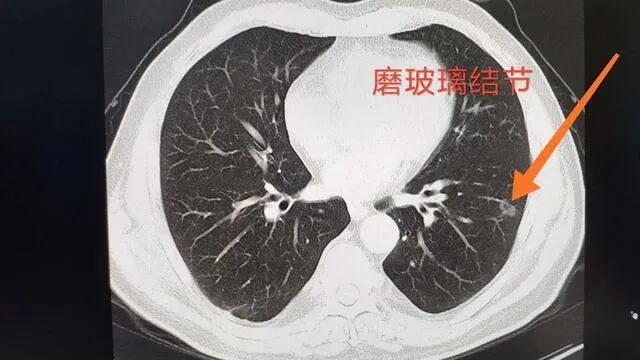

有些磨玻璃结节其实是没有意义的,比如3毫米的实体结节;一些磨玻璃肺结节是早期癌症,如磨玻璃结节,需要专业医生的专业判断。有人认为,发现肺结节后,不管是好是坏,都应该尽快手术切除,防止其将来发展为癌症。这种观点是不正确的。

一些肺结节需要积极手术,而另一些则需要保守治疗。手术方法也可能因结节的位置、形状、动态变化以及患者的个人情况而异,这需要综合判断。例如,直径8mm及以上的混合磨玻璃结节、直径1cm及以上的磨玻璃结节和直径1.5cm及以上的实体结节都是高危结节。

有必要警惕他们可能是肺癌癌症,不要忽视他们。至少,应该动态地观察它们的变化。毛章凡在总结日常经验时,根据肺结节的大小对其进行了简要的分类介绍,希望能为市民提供一些参考。